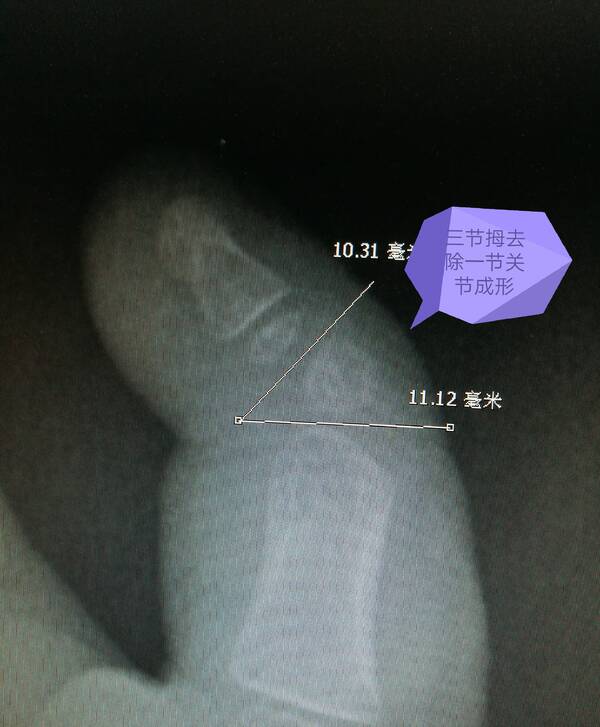

桡侧多指切除截骨矫形术